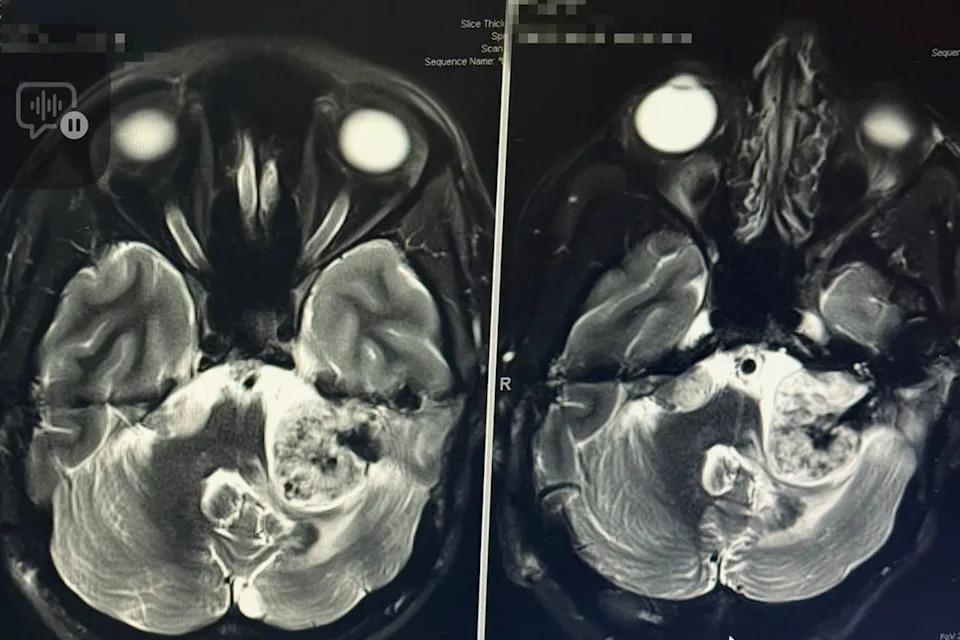

“I went for a dive and hit my head on the ground. So I went in for a routine MRI,” McKinnon Galloway, now 33, told SWNS via the New York Post. It was during that scan that doctors told the teen from Charlotte, N.C., she would be “completely deaf” by the time she graduated high school, due to two tumors that were pressing down on nerves in her brain.

The tumors were caused by neurofibromatosis type 2, a genetic disorder that causes tumors to grow on nerves. Galloway was put on medication to help slow their growths, but eventually needed multiple brain surgeries to manage their progression.

McKinnon Galloway lives with 13 tumors, including 2 in her brain

Credit: McKinnon Galloway / SWNS

While “I just got my first stable scan in four years,” she says she’s worried about the future as she lives with 13 tumors — six in her spine, three on her hand, two in her neck, and two in her brain.